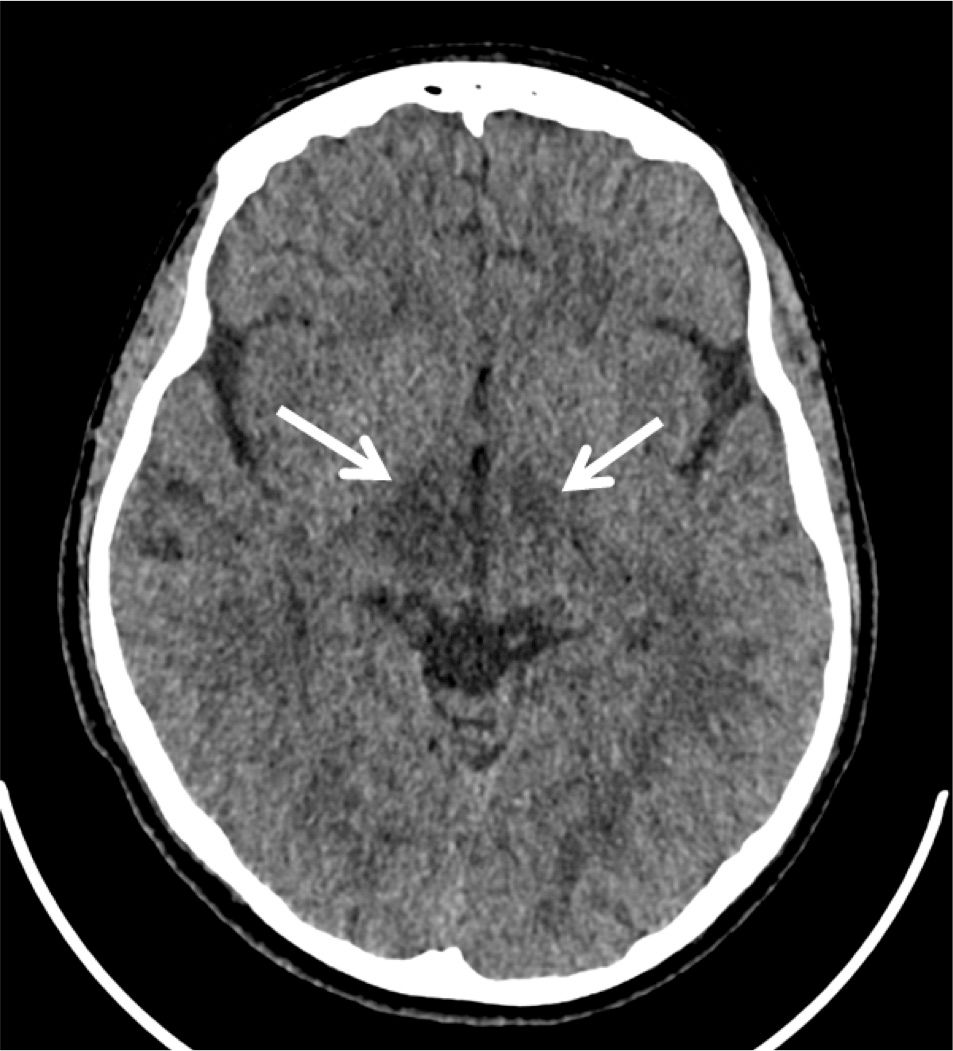

Video EEG at our institution did not demonstrate evidence of seizures. Head computed tomography (CT) on admission showed hypoattenuation in bilateral thalami, though more on the right side as compared to the left side. Magnetic resonance imaging (MRI), magnetic resonance angiogram, and magnetic resonance venography were done given concern for vasculitis and significant for hyperintensity flair in the medial thalami/massa intermedia. Urine toxicology screen was negative. A lumbar puncture showed a high opening pressure and cerebrospinal fluid (CSF) pleocytosis with white blood cells of 26, suggesting infectious versus autoimmune processes. Further infectious work-up, including a complete blood count, procalcitonin, meningitis/encephalitis panel, antistreptolysin O (ASO) titer, group A streptococcus direct DNA probe, rapid plasma regain (RPR), Epstein-Barr virus, Lyme disease titers, HIV, quantiferon gold, Bartonella antibodies, and herpes simplex virus (HSV) antibodies were all negative. Rheumatologic workup, including erythrocyte sedimentation rate, c-reactive protein, antinuclear antibody, anti-ds DNA, C3, C4, proteinase-3 antibody, myeloperoxide antibody, and centromere antibody were unrevealing. A comprehensive metabolic panel, lactic acid, ammonia, thyroid stimulating hormone (TSH), free T4, vitamin B1, ceruloplasmin, and copper studies did not demonstrate a toxic or metabolic cause. A CT abdomen and pelvis was done to rule out an oncologic process and was within normal limits. Alpha-fetoprotein was normal. An autoimmune and paraneoplastic panel was sent from the CSF, however results were not available during the patient’s hospital admission.

Laboratory evaluation was largely unrevealing, except for slight CSF pleocytosis. This, along with the CT and MRI findings and the clinical picture of waxing and waning aggression, agitation, and insomnia was concerning for autoimmune encephalitis. One week after discharge, CSF studies returned positive for anti-NMDAR and anti-MOG antibodies.

Figure 2